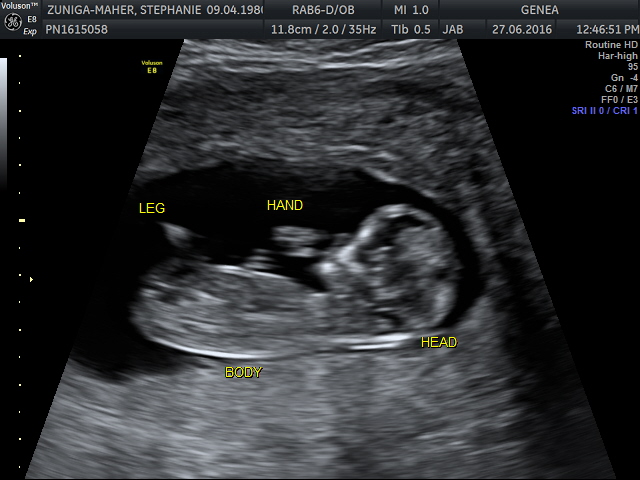

Actually has nothing to do with cooking or triathlons, but it promises to be life changing…. And it’s due to arrive in January 2017.

We’re obviously thrilled to welcome our new little cook/triathlete into the world and really excited to share our newest project with you!

I think if you look closely, it’s already practicing cycling in the video- and yes, it’s a bit alien like at the moment, but we fully expect him (or her) to only get cuter from here!